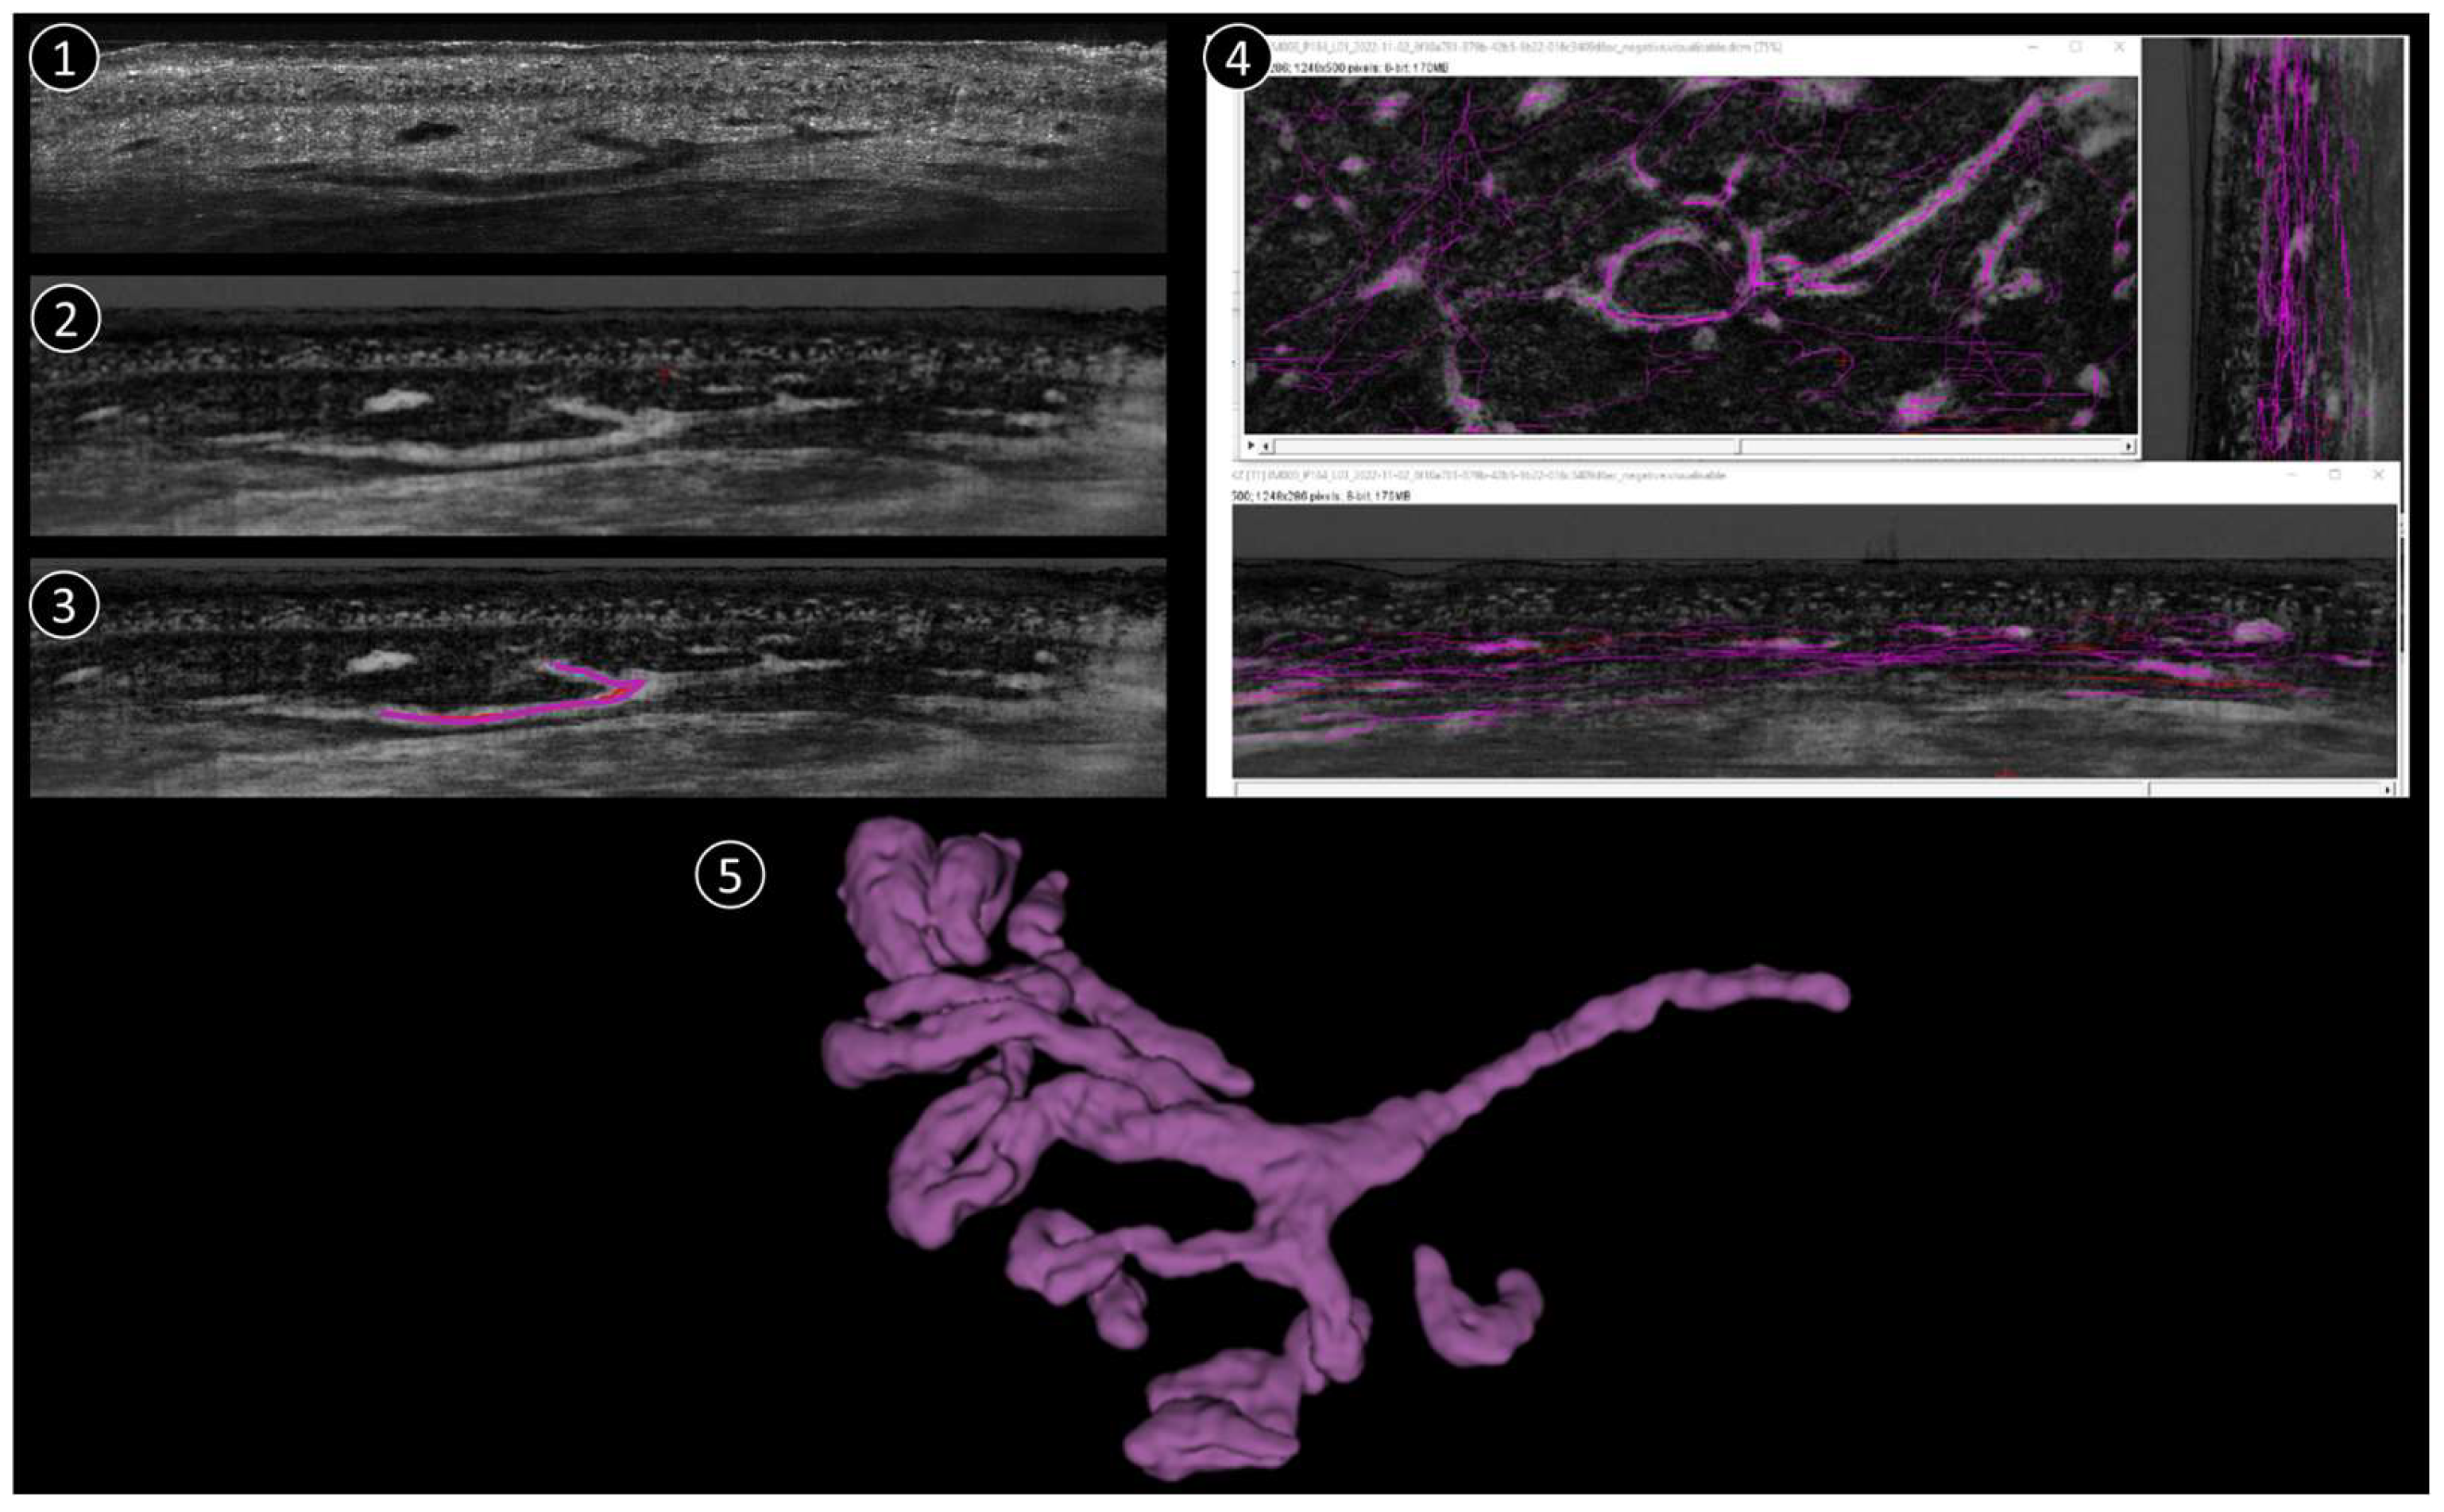

The process of reconstructing and visualising vascular structures from the aforementioned 3D stack mode comprises three primary steps (Figure 1):

Figure 1.

Schematic reconstruction process. 1: Original LC-OCT image (vertical). 2: Negative LC-OCT image (vertical). 3: Segmentation drawn on LC-OCT images (vertical). 4: Final skeleton after segmentation applied in all 3 orientations (vertical, coronal, horizontal). 5: 3D reconstruction example.

(1) To improve the visibility of the vascular structures within the 3D image stack, the original stack is first converted into a “negative” image. In this context, the term “negative” refers to the inversion of pixel intensities, whereby structures that were originally darker become lighter and vice versa. This conversion is crucial as it allows vessels that may have appeared darker in the original stack to become more prominent and easier to recognize in the subsequent steps.

(2) After converting the image stack to a negative, the next step is to manually trace the vessel structures. The Simple Neurite Tracer (SNT) plugin in the ImageJ software (1.54k) used for this purpose. The SNT plugin is a versatile tool designed for tracing and analyzing tubular structures in 3D images, making it ideal for this application. The manual tracing process is performed in three different orientations of the image stack to ensure comprehensive coverage of the vascular network (sagittal, frontal, and horizontal). The stack is viewed from the side, providing a vertical cross-section. From the front, it provides a vertical cross-section in the coronal plane and it is viewed from above, providing a horizontal cross-section in the transverse plane. In each projection, the skeleton of each vessel is drawn manually by carefully following the course of the vessels throughout the 3D volume. This process is repeated for each vessel within the stack to ensure that the entire vascular network is accurately traced.

(3) Once manual tracing is completed in all three projections, the traced vessel skeletons are used to create a binary mask. This binary mask represents the vessel structures as a binary image in which the vessels are mapped as white pixels (value 1) against a black background (value 0). The binary mask is then smoothed to refine the representation of the vessels and remove any irregularities or artifacts that may have occurred during manual tracing. This smoothing step is crucial for a clean and accurate 3D representation of the vessel architecture.

Finally, the smoothed binary mask is used to reconstruct a 3D model of the vascular network. This 3D architecture provides a detailed and comprehensive visualization of the vessels that can be further analyzed or used for various applications such as the study of vessel morphology or the quantification of vessel parameters. One 3D corresponds to 1200 coronal images + 500 vertical images + ~400 horizontal images (the number of horizontal images depends on how deep the 3D was taken). The full process takes approximately 1h per stack, depending on the complexity of the vascular structure.